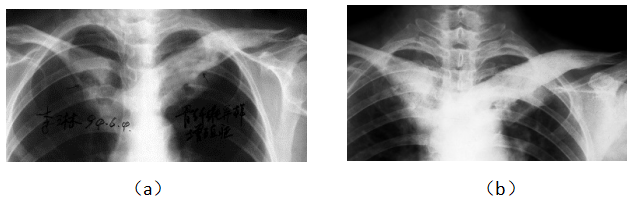

病例1女,51岁,患病4年,治疗12个月后痊愈。治疗前,股骨头顶部呈V形缺损,边界和骨密度不均匀(a)。治疗8个月后,坏死面积变小,骨密度降低,密度均匀(b)。股骨头表面光滑,坏死区消失,可见恢复过程的低密度区(c)

Case 1 female, 51 years old, 4 years old, recovered after 12 months of eating. Before eating, the top of the femoral head was V-shaped defect, with uneven boundary and bone density (a). After 8 months of consumption, the necrotic area became smaller and the bone density decreased, but it was more uniform (b). After eating, the head was smooth, the necrosis area disappeared, and the low density area (c) of the recovery process could be seen

| (b) | (b) | (c) |